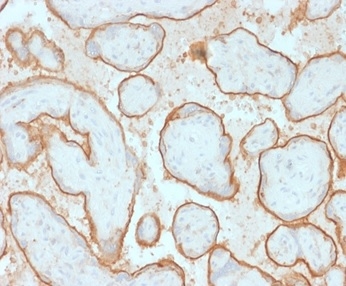

Formalin-fixed, paraffin-embedded human placenta stained with EGFR Mouse Monoclonal Antibody (GFR/2341).

This MAb recognizes a protein of 170kDa, identified as EGFR. EGFR is type I receptor tyrosine kinase with sequence homology to erbB-1, -2, -3 -4 or HER-1, -2, -3 -4. It binds to Epidermal Growth Factor (EGF), Transforming Growth Factor-a (TGF-a), Heparin-binding EGF (HB-EGF), amphiregulin, betacellulin and epiregulin. EGFR is overexpressed in tumors of breast, brain, bladder, lung, gastric, head & neck, esophagus, cervix, vulva, ovary, and endometrium. It is predominantly present in squamous cell carcinomas.